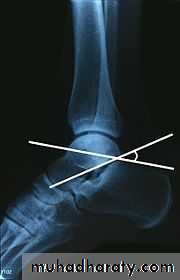

Calcaneal fracture, also known Don Juan fracture, is a fracture of the calcaneus. It is usually caused by a fall from height when one lands on their feet. These fractures represent approximately 2% of all fractures but 60% of tarsal bone fractures.